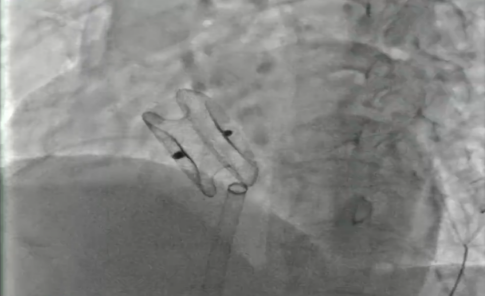

成功封堵

我院心血管内科介入团队经详细评估后,开展了充分的术前讨论,决定为张阿姨行“室上速射频消融手术+房间隔缺损封堵术”的一站式手术。该方案通过介入微创实施,一个小穿刺点伤口完成两个手术,不仅大大减轻分次手术给患者带来的痛苦及经济负担,而且术后恢复快。最终手术成功实施,术后第二天患者即可下床活动。